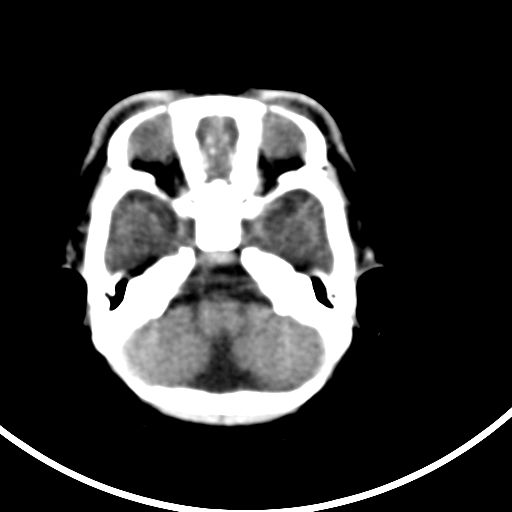

新生儿3天,超过预产期5天剖宫产,有缺氧病史,具体评分不详,现反应差,肌张力低,前囟平,原始反射存在,无苦闹等。

颅底骨质影,正常颅脑表现。

kaolv小脑幕,后纵裂区蛛网膜下腔出血;轻度脑肿胀